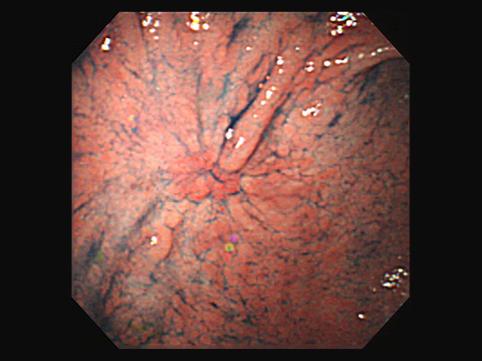

질환(병리주체)의 분류 악성 상피성종양/선암

부위(장기별) 위(부위)/위각

검사방법 내시경

종양의 육안분류 0형(표재형)/IIc형(IIc)

종양의 최대경(밀리미터) 30~34

종양의 심달도 m